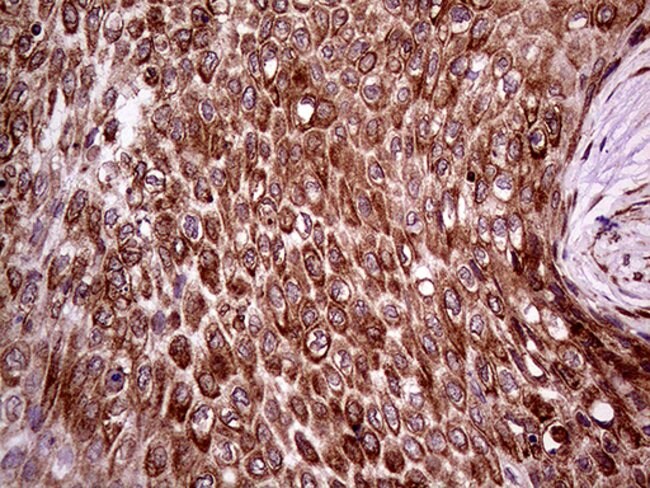

ERLIN1 Monoclonal Antibody (OTI4B1), TrueMAB™, OriGene

Supplier: OriGene TA809148

Component of the ERLIN1/ERLIN2 complex which mediates the endoplasmic reticulum-associated degradation (ERAD) of inositol 1,4,5-trisphosphate receptors (IP3Rs). Involved in regulation of cellular cholesterol homeostasis by regulation the SREBP signaling pathway. Binds cholesterol and may promote ER retention of the SCAP-SREBF complex.Specifications

Immunohistochemistry (Paraffin), Western Blot | |